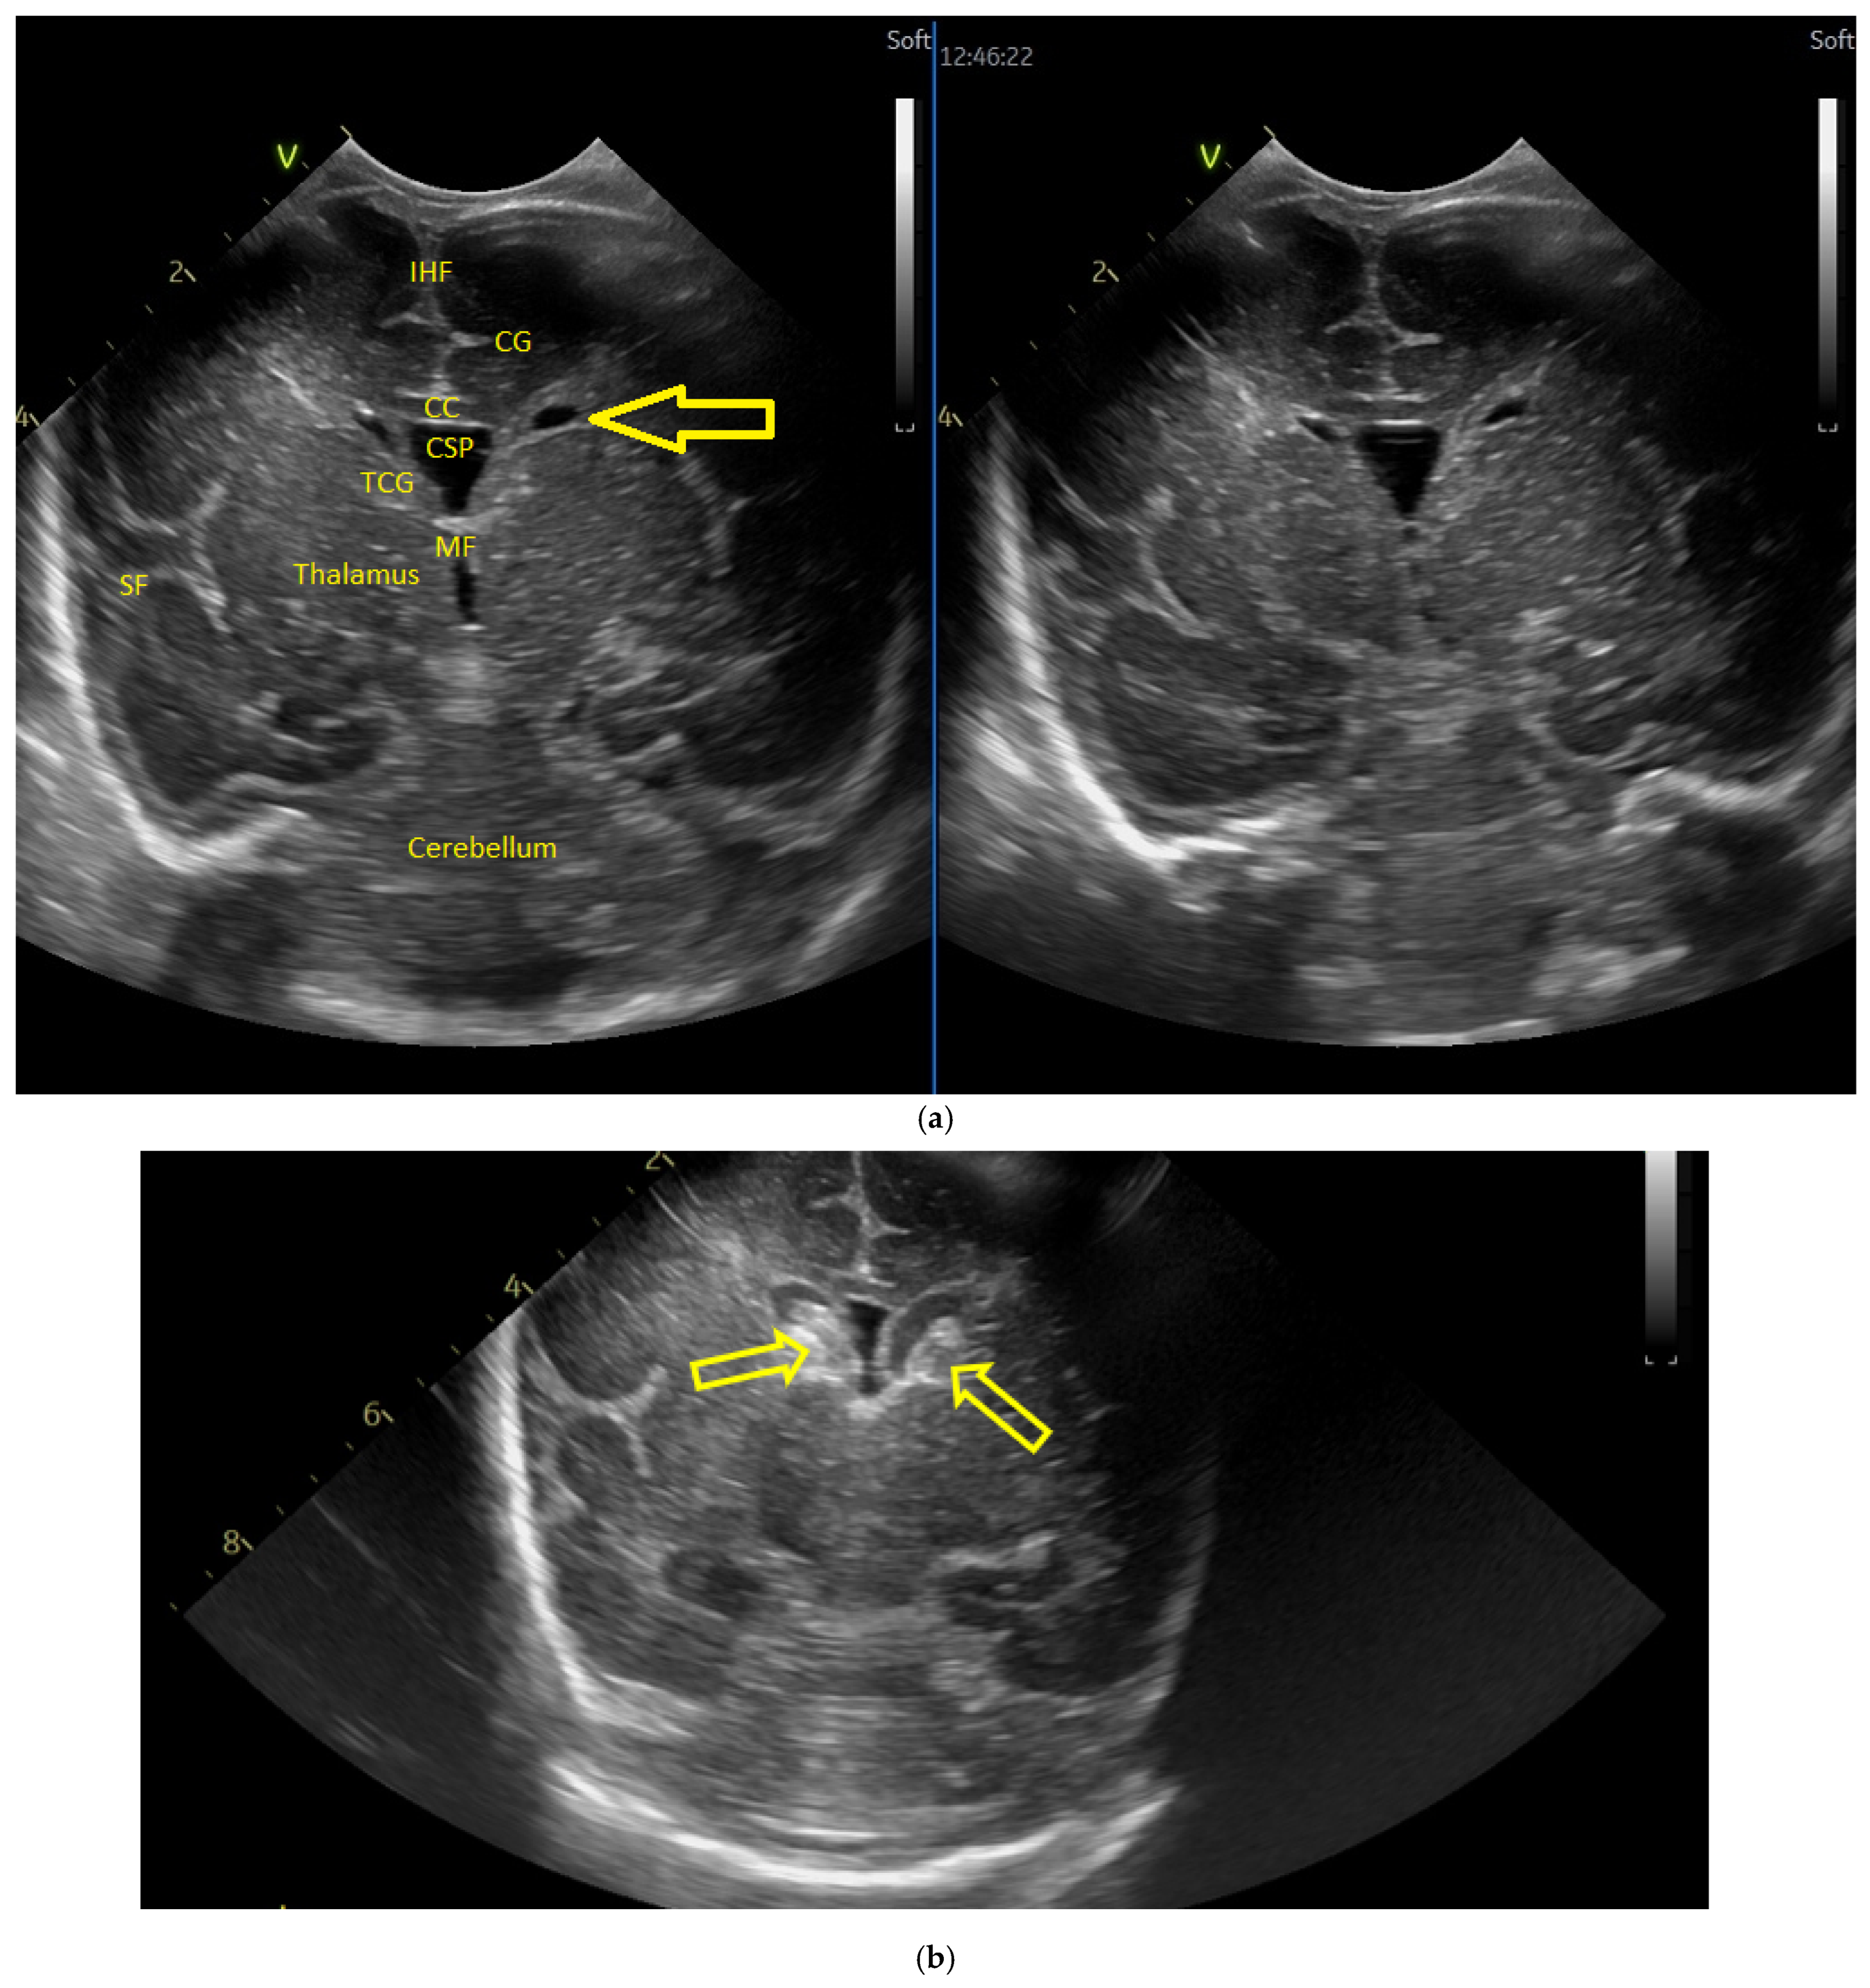

(a) Cranial ultrasound. Coronal view. Enlargement of the lateral ventricles with hyperechoic and third ventricle dilation. D1, D2—Levine index measurement. D3, D4—anterior horn width measurement. D5—third ventricle (personal image collection). (b) Cranial ultrasound. Sagittal view. Up—left ventricle. D1, D2—lateral ventricle measurements and thalamo-occipital horn width. Down—right ventricle. D1, D2—lateral ventricle measurements and thalamo-occipital horn width (personal image collection). (c) Cranial ultrasound. Sagittal view. Up—enlargement of the third and fourth ventricles. Measurements of the ventricles. Down—measurement of the resistive index (RI) performed on the anterior cerebral artery (ACA) using Doppler flow measurements. RI—0.74 (personal image collection). (d) Cranial ultrasound. Transtemporal view. Yellow arrow—enlargement of the Sylvian aqueduct (personal image collection). (e) Cranial ultrasound. Sagittal view. Yellow arrow—arachnoid cyst posterior to the third ventricle (personal image collection). (f) Cranial ultrasound. Coronal view. Lateral ventricles and third ventricle enlargement. D1, D2—Levine index measurement. D3, D6—right lateral ventricle measurement (anterior horn width). D4, D5—left lateral ventricle measurement (anterior horn width) (personal image collection). (g) Cranial ultrasound. Sagittal view. Left—left ventricle. D1—thalamo-occipital distance measurement. Right—right ventricle. D2—thalamo-occipital distance measurement (personal image collection). (h) Cranial ultrasound. Coronal view. Up—orange arrow—third ventricle. Red arrow—fourth ventricles. Yellow arrow—arachnoid cyst. Down—resistive index measured on the anterior cerebral artery. RI—0.79 (personal image collection). (i) Cranial ultrasound. Transversal view. Up—RI precompression value on the middle cerebral artery performed with Doppler examination. RI—68. Down—RI post-compression value on the middle cerebral artery performed with Doppler examination. RI—0.79 (personal image collection). (j) Cranial ultrasound. Up—coronal view. L1, L2—Levine index measurement of the lateral ventricles. Down—sagittal view. L1, L2—measurement of the thalamo-occipital distance (personal image collection). (k) Cranial ultrasound. Sagittal view. L1, L2—measurement of the third ventricle. L3, L4—measurement of the fourth ventricle. L5, L6—measurement of the arachnoid cyst (personal image collection). (l). Head circumference-for-age. “X” symbols represent the measurements performed from birth and follow-up examinations. Head circumference was still under the curve during follow-up examinations (personal image collection) [28].

The CUS examination performed at 48 h after birth showed increases in the diameters of all ventricles. The resistive index presented an increase as well. The bregmatic fontanelle started bulging. The dimensions of the Sylvian aqueduct were not modified (Figure 3f–h).

The CUS examinations performed at four days and seven days after birth showed stabilization regarding the values of the diameters. The pre- and post-compression values of the resistive index of the middle cerebral artery showed a delta-RI of 0.11 (pre—0.68, post—0.79, Figure 3i).

After discharge, at three weeks after birth (follow-up examination), the ventricle measurements showed wider ventricles and the arachnoid cyst was still present (Figure 3j,k).

The next follow-up examination performed a week later showed a delta-RI of 0.12 and an increase in the cranial perimeter (+ one cm since the last follow-up).

At 12 weeks of life (five week corrected age), ventricle dilations were still present. Neurological examinations showed axial and limb hypotonia. The general movement examination showed a poor repertoire with a General Movement Optimality Score (GMOS) of 19. At 18 weeks of life (11 week corrected age), the neurological exam revealed that the infant presented plagiocephaly and could keep eye contact, and during the traction-to-sit maneuver showed hypotonia of the neck muscles. In the prone position, the infant was unable to hold the head up. The passive tone assessment showed the “scarf sign”, with the elbow at the midline bilaterally and a popliteal angle of 90° on the right and 110° on the left. Deep tendon reflexes were present. The general movement (GM) assessment revealed absent fidgety movements, with a Motor Optimality Score (MOS) of 13.